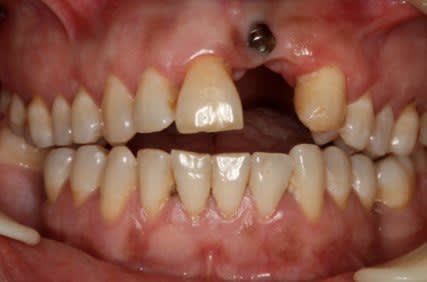

Mais un patient est arrive au cabinet avec 7 Implants maxillaires et rien de plus, bilan des courses , 2 mobiles, 2 avec l'hexagone externe cassé, 1 avec la vis prothétique cassée dans l'implant. Il reste un en place de 17 a moitie enterré et l'autre en 16, ni l'un i l'autre ont une vis de couverture ou un piler de cicatrisation.

P.S : Pour le fun le cas pour lequel , je suis énervé et celui du proces est pire mais je ne peux pas le publier.

Il a laissé la patiente 5 mois comme ça en disant que tout allait bien, l'endo je l'ai faite moi au cas ou !!

Le second va être virer aussi car il est intra-sinusien générant une sinusite chronique.